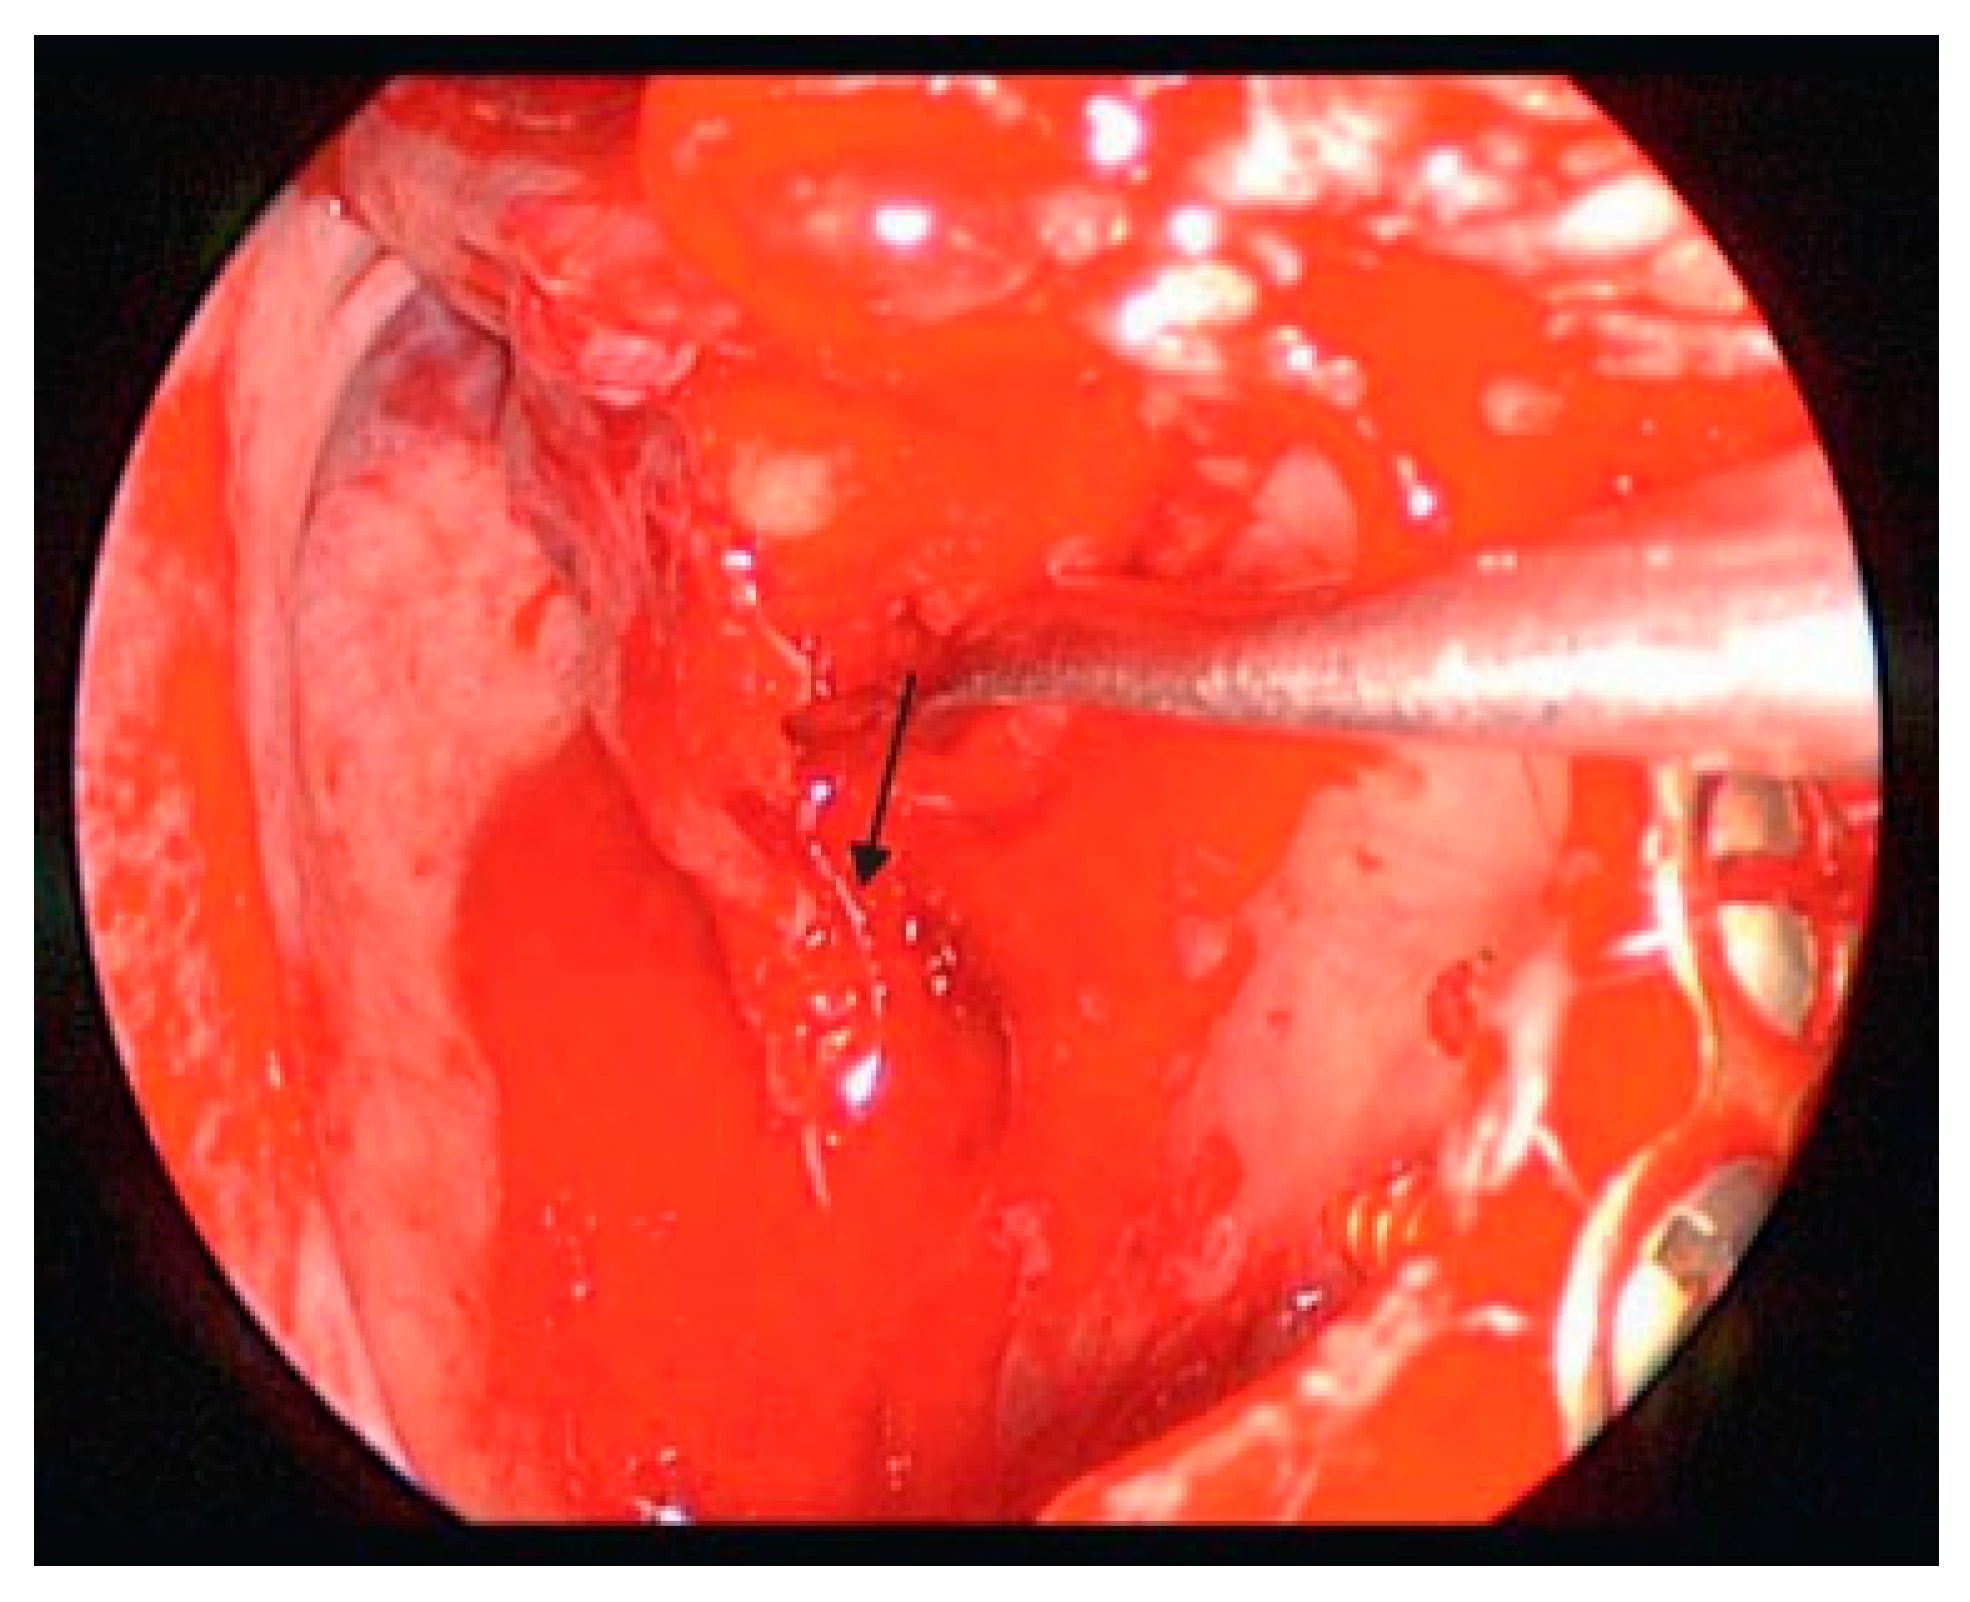

Figure 9. Uncinate to the left upfront, bulla taken down, and the anterior ethmoid exposed.